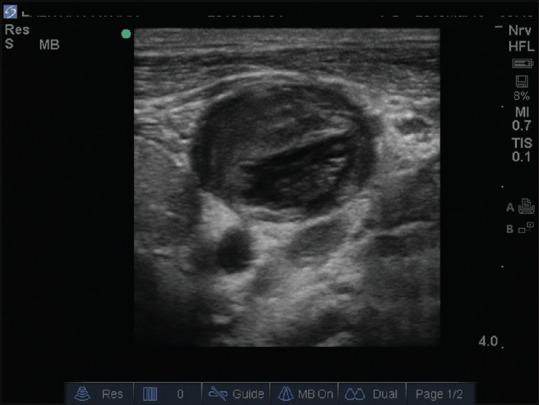

We are reporting two cases of neck and arm major venous thrombosis in patients of posttubercular chronic constrictive pericarditis posted for pericardectomy. There was unanticipated difficulty in placement of Internal Jugular vein catheter and subsequent ultrasound revealed thrombosis in the major veins. It was not diagnosed in the preoperative period. This report raises this major complication and highlights the use of ultrasound in such scenarios.

我们报告了两例患有结核后慢性缩窄性心包炎、计划进行心包切除术的患者发生颈部和手臂大静脉血栓形成的病例。颈内静脉导管置入过程中出现了意外困难,随后超声检查显示大静脉内有血栓形成。术前未诊断出该情况。本报告提出了这一主要并发症,并强调了超声在此类情况下的应用。